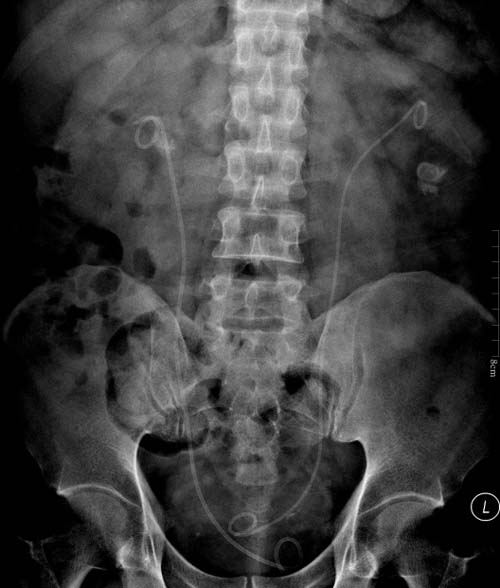

入院后检查发现,患者双侧输尿管见双J管影,右侧肾结石大小1.2×1.5cm,左侧肾结石大小1.6×2.0cm。由于患者为冠状动脉支架置入术后冠心病患者,科室讨论后决定对患者分两步实施治疗,首先处理右侧上尿路结石,拔出在当地无法拔出的右侧输尿管支架管,使用一次性电子输尿管软镜行右侧肾结石钬激光碎石术;第二步拟两周后处理左侧上尿路结石,使用一次性电子输尿管软镜行左侧肾结石钬激光碎石术。

术前患者KUB